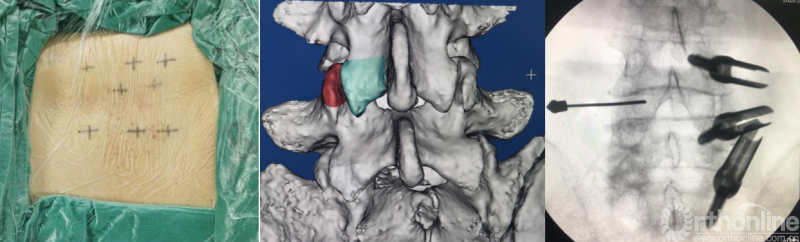

BELIF技术十步法

详细步骤:一定、二剥、三凿、四分、五咬、六切、七牵、八铰、九填、十置

第一步“定”:X线定位在上位椎体下关节突下三分之一部;

第二步“剥”:剥离器+射频剥离、止血、造腔,显露下关节突尖部;

第三步“凿”:凿除部分下关节突;

第四步“分”:分离上关节突及黄韧带;

第五步“咬”:咬除部分上关节突,显露椎间盘及神经根;

第六步“切”:切除椎间盘;

第七步“牵”:神经拉钩牵拉保护神经根;

第八步“铰”:铰刀置入处理上下终板(刮勺置入处理终板);

第九步“填”:椎间隙填塞植骨;

第十步“置”:置入融合器、经皮钉。